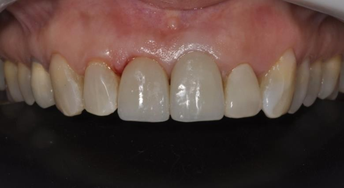

Patient I. A., female, 47 years old, attended the dental office with the chief complaint of dissatisfaction with her anterior teeth and smile. On clinical examination a ceramic veneer was found on tooth 11 with altered color, irregular shape and contour, and on tooth 21 an all-ceramic crown with altered color was found. Both restorations had different colors and volumes, as well as the gingival apex on both teeth was discrepant (Figures 1-3).

Figure 1 Initial photograph showing the discrepancy in color, shape and size between the restorations.

Figure 1 Initial photograph of the smile.